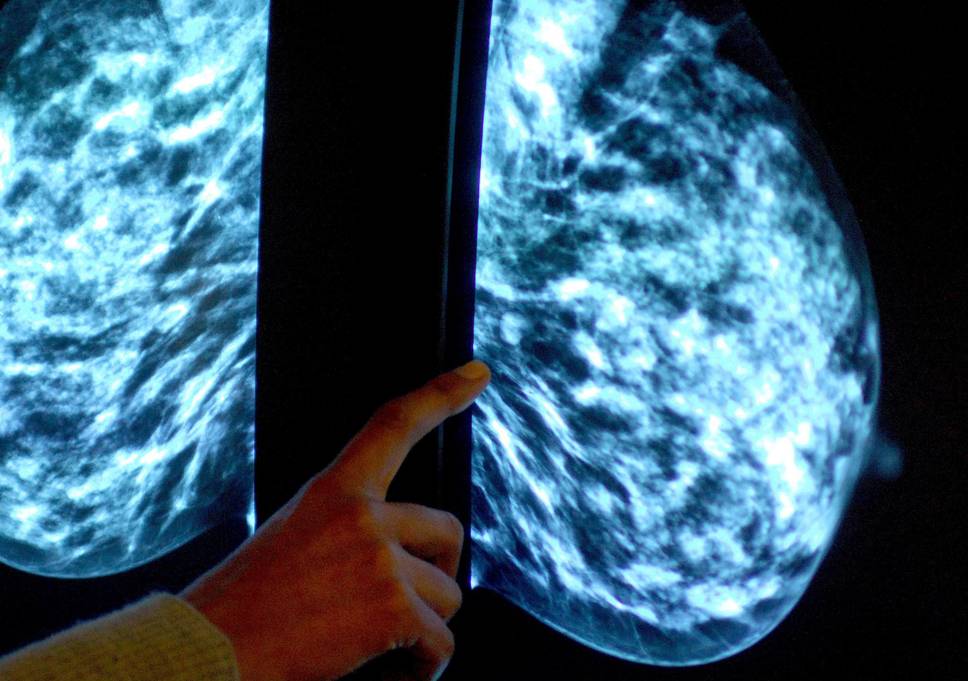

La plupart des femmes atteintes d'un cancer du sein au stade précoce peuvent être en mesure d'éviter la chimiothérapie, selon une nouvelle étude.

L'étude a révélé que les tests génétiques sur les échantillons de tumeurs étaient en mesure d'identifier les femmes qui pourraient éviter la chimiothérapie en toute sécurité et de prendre seulement un médicament qui bloque l'hormone œstrogène ou qui empêche le corps de le faire.

Le médicament inhibiteur des hormones, le tamoxifène et les médicaments apparentés, appelé "thérapie endocrinienne", est devenu une partie essentielle du traitement pour la plupart des femmes, car il réduit les risques de récidive, de nouvelles tumeurs mammaires et de décès dus à la maladie.

Toutefois, les résultats peuvent ne pas s'appliquer à ceux qui ont de plus grandes tumeurs ou ceux avec le cancer qui a commencé à se propager, selon les experts.